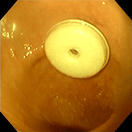

胃瘻チューブ設置

‣内視鏡的治療について

緊急時の異物摘出はもちろん、胃瘻チューブの設置、食道狭窄に対する食道拡張術、ポリペクトミーなど、使用は多岐にわたります。